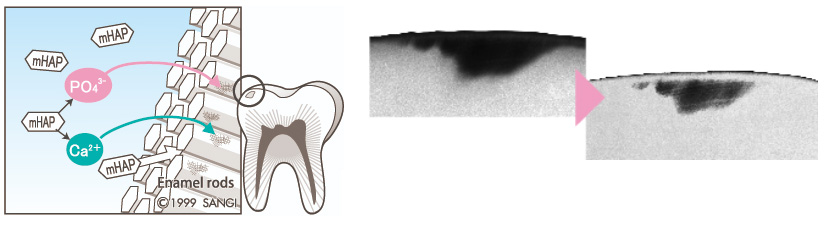

치아와 뼈를 구성하는

하이드록시아파타이트

치아영양제 아파프로는

치아와 뼈를 구성하는 주성분인 하이드록시아파타이트를

함유한 치면수복용 제품입니다.

아파프로에 함유된

'의료용 나노 하이드록시아파타이트 Nano<mHAP>'는

치면의 표면강도를 높이고

법랑질의 투명도와 자연치아 본연의 광택을 살리는

목적으로 사용합니다.

3️⃣ 초기우식 치료

화이트스팟과 같이 법랑질의 미네랄이 녹아

초기우식의 탈회가 진행된

치아표면에 미네랄을 보급하여

재석회화를 촉진합니다.